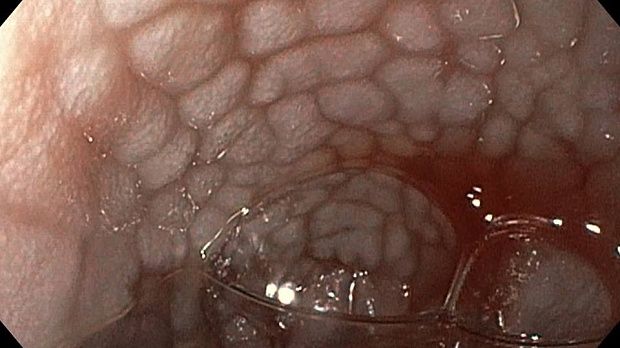

Публикации из социальных сетей: “Cobblestone esophagitis” (эзофагит со слизистой булыжной мостовой)

“Cobblestone esophagitis” (эзофагит со слизистой булыжной мостовой) - редкая эндоскопическая находка и ассоциируется с эозинофильным эзофагитом, кандидозом и пищеводом Барретта у взрослых. Он также может быть найден при тяжелом рефлюкс-эзофагите, вторичен к дистальной обструкции гастроинтестинального тракта. В нашем случае - это пациент после с 9-летним стажем бандажирования кардиального отдела желудка, признаками дуоденостаза, фундальной эрозивной гастропатией, расширением пищевода и уровнем жидкости в нем при горизонтальном положении, грыжи ПОД, эрозивно-язвенном дистальном эзофагите.. Пациент просто пришел удалить полип в прямой кишке и заодно посмотреть, что творится в желудке.... Ацетообеление+NBI+биопсия. ИПП на 3-4 мес и повтор для решения о Барретте.